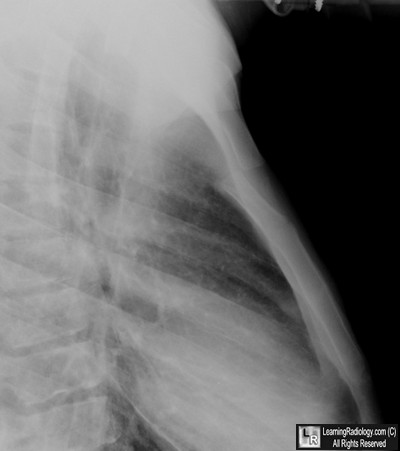

Case of the Week 489

What is the most likely diagnosis?

• 43 year-old in motor vehicle accident 2 months earlier

Close-up of lateral radiograph of chest

5. Sternomanubrial Dislocation

Sternomanubrial Dislocation

• Rare

• Usually occurs with high energy impact, such as motor vehicle accidents

• Can occur with lower impact forces if there is a pre-existing arthropathy, e.g. rheumatoid arthritis or severe kyphosis

• Joint may be synovial (dislocation most common), synchondral, or synosteal (latter two typically fracture through manubrium without dislocation)